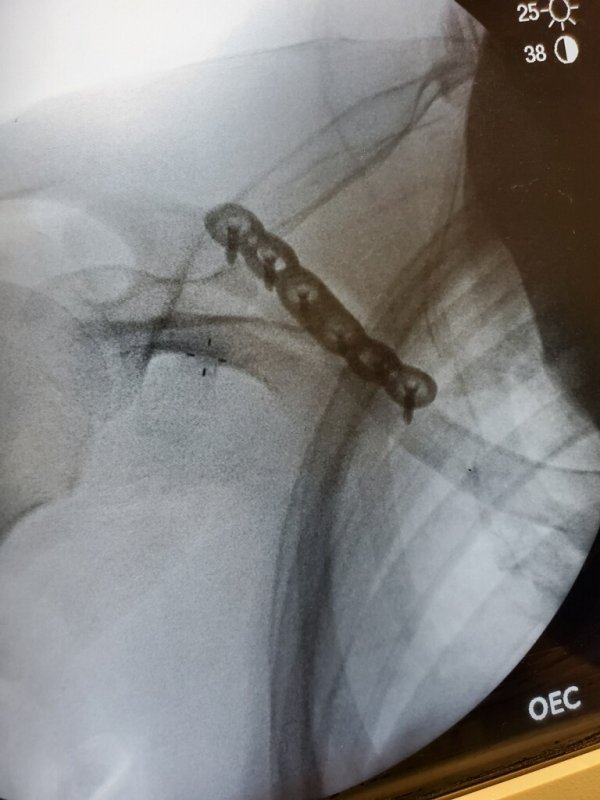

CR is loose! I did this yesterday on the new loop on the far side of Gilbride. Back and head are 100% fine so could have been much worse.

View attachment 129009View attachment 129010